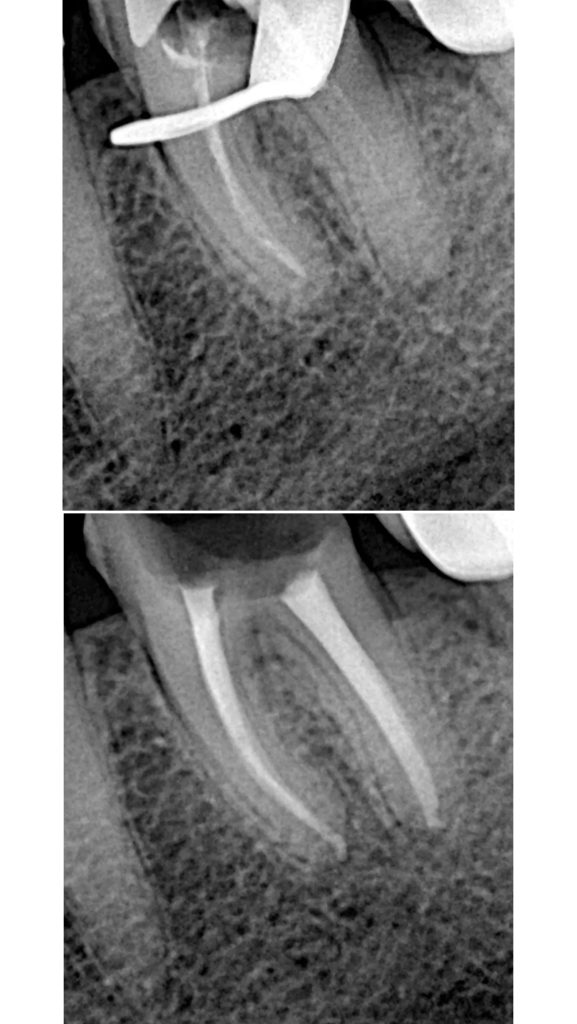

• Диагностика и лечение кариеса и его осложнений (пульпиты, периодонтиты)

• Эндодонтическое лечение корневых каналов с использованием стоматологического микроскопа